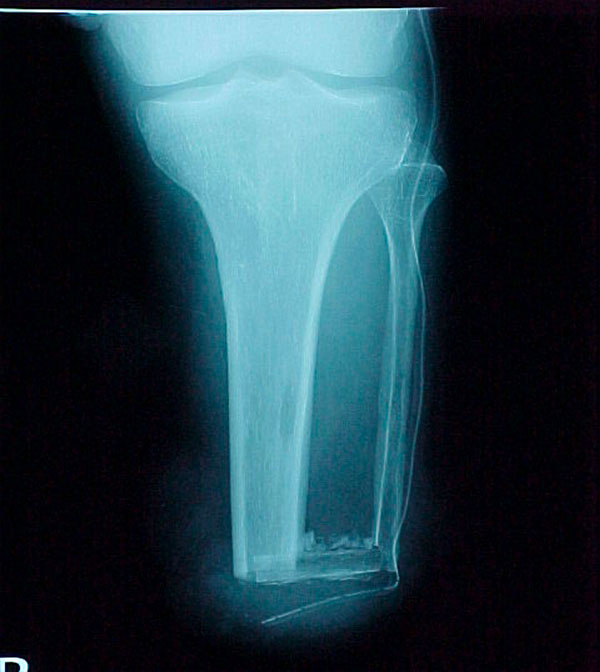

- Focus Area Reconstructive Surgery & Non-Surgical Management to Improve Bone Healing

- Sponsor DoD PRORP

- Primary Objective To define a serum protein based diagnostic for the progression and failure of fracture healing, though the identification of a set of serum proteins that appear at early times of biological healing and show a specific correlation with later radiological and functional signs used to define delayed healing and non-union.